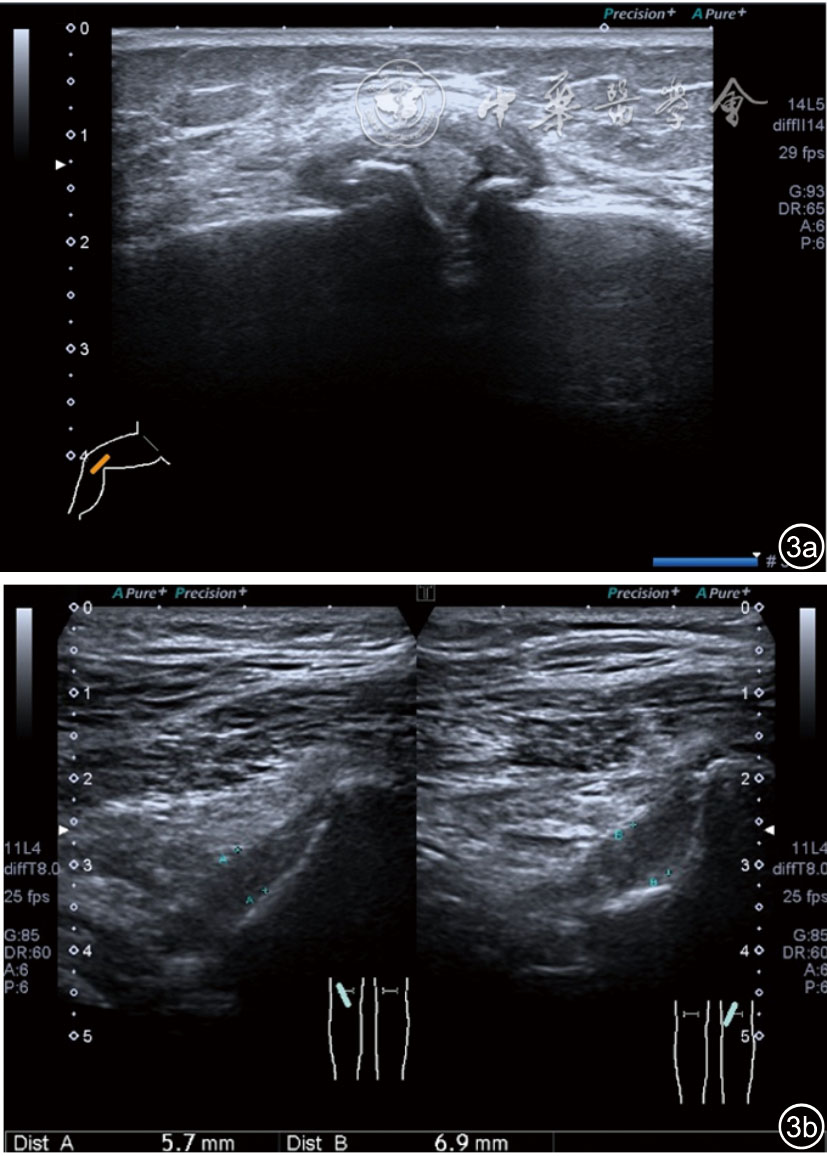

患者采取侧卧位,患肢在上,屈膝20°。应用10~18 MHz高频线阵探头,扫查深度1~3 mm。长轴和短轴结合双侧对比扫查。超声影像学所见:短轴可见卡压腓总神经近端增粗,面积增大;长轴可见腓总神经卡压处变细,其近侧肿胀、回声减低,而在卡压远侧则表现正常(图35);一些受压严重者可以出现神经周围积液,卡压神经部位的筋膜增厚(图36);受压神经内血流增加对临床诊断意义更大(图37);探头在病变神经处加压常可引起神经刺激症状。腓总神经支配的肌肉有失神经支配改变,表现为肌肉回声增高和肌肉萎缩(图38)。

图38 肌肉回声增强和肌肉萎缩超声图像